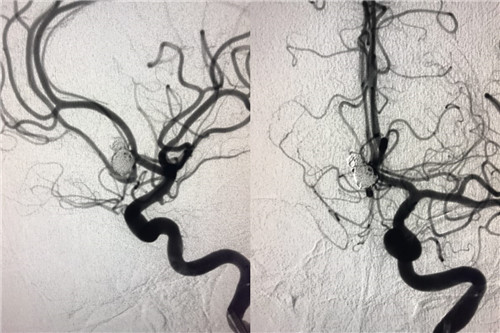

术后造影

患者赵某,8月28日因“蛛网膜下腔出血”入住我院神经外科。入院时意识呈浅昏迷,且意识障碍进行性加重伴随右侧瞳孔散大,曲友直教授团队根据颅脑CT判定患者为动脉瘤引起的蛛网膜下腔出血。由于动脉瘤在人体内像个定时炸弹,随时会再次破裂,危险性非常大。能否及时为患者实施动脉瘤手术,避免动脉瘤继续破裂,从源头遏制患者病情继续恶化的可能性,直接关系到患者的预后。曲教授团队制定了详细的诊疗计划,在最短时间内为患者行侧脑室外引流术,并及时为患者实施了全脑血管造影,结果证实了术前判断,是大脑前交通动脉瘤,分上下两叶、宽颈。考虑到患者脑肿胀明显,基础状态差,急诊行开颅夹闭手术风险极高,曲友直教授团队反复评估、综合考虑后为患者实施了双导管技术宽颈动脉栓塞术。实施双导管技术避免支架辅助对前交通宽颈动脉瘤进行栓塞,术后患者无须长期口服抗血小板及抗凝药物、为患者术后赢得了进一步康复的机会、减少了长期服药的经济负担。手术过程十分顺利,术后患者病情稳定,正在进一步恢复治疗中。